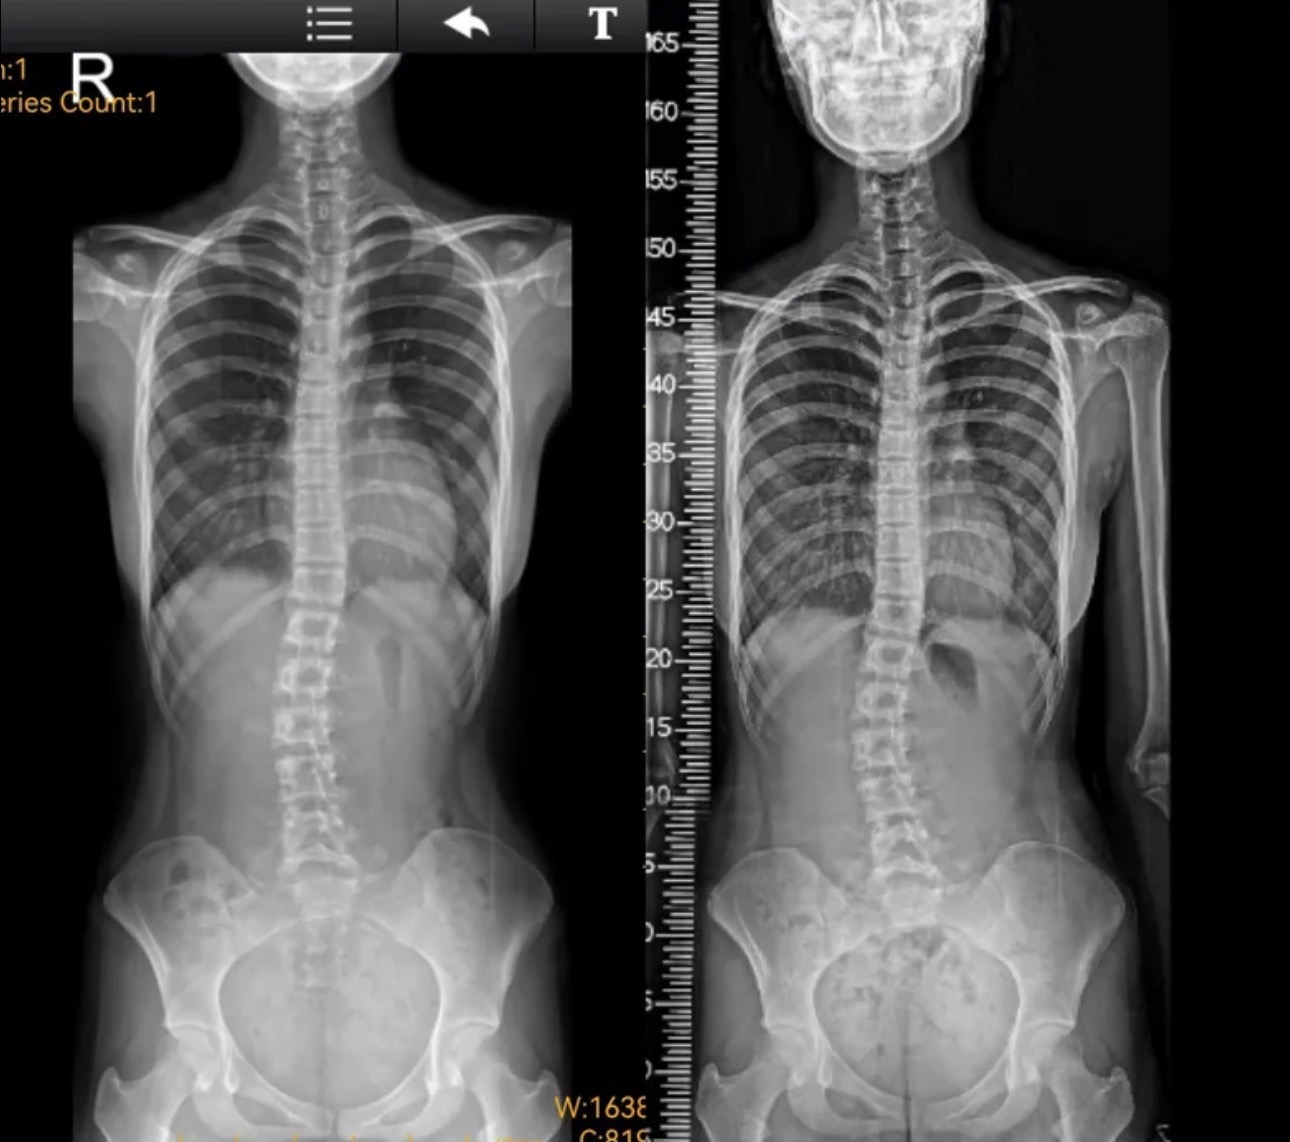

衷德脊柱,我们只关注侧弯保守治疗~

Zhongde Spine, bending no breaking ~